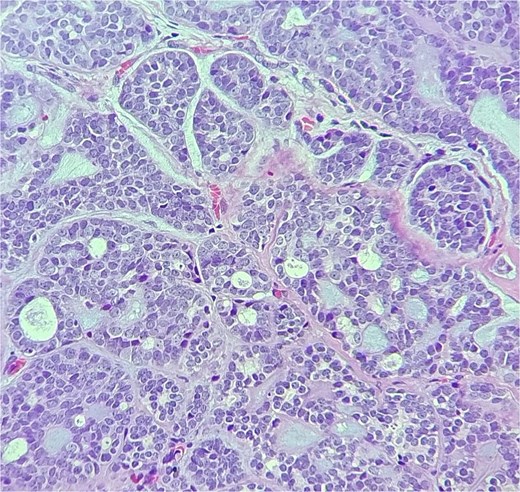

Histopathologic examination showed ACC displaying multiple cribriform structures composed of epithelial and basal/myoepithelial cells (Fig. 2). Molecular profiling indicated negative estrogen receptor, progesterone receptor, HER2, and PDL-1.

The tumor is composed of dual cell populations of basaloid epithelial cells and myoepithelial cells, arranged in characteristic cribriform and tubular growth patterns.

ACC primarily originates from the epithelial cells of the lacrimal gland and exhibits histopathological similarities to ACC found in salivary glands. The key histological patterns—cribriform, tubular, and solid—provide diagnostic specificity, with the cribriform pattern being the most prevalent and linked to a more favorable prognosis compared to the solid subtype [3]. ACC of the lacrimal gland presents with proptosis, pain, and diplopia, showcasing aggressive behavior and parotid metastasis via lymphatic or hematogenous routes.